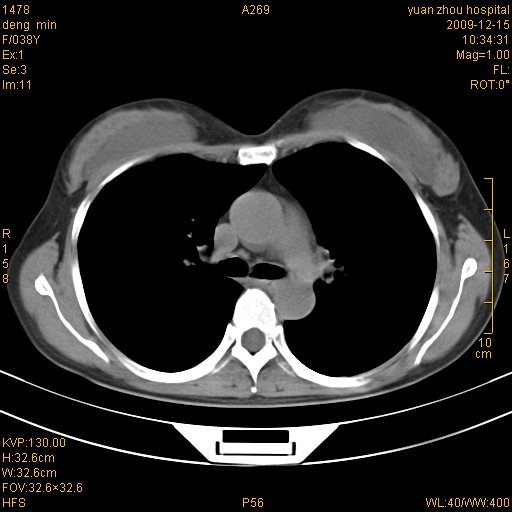

标题: CT23919:F38Y 咳嗽月余 [打印本页]

标题: CT23919:F38Y 咳嗽月余

右肺中下叶、左肺上叶舌段及左肺下叶支气管扩张合并感染。